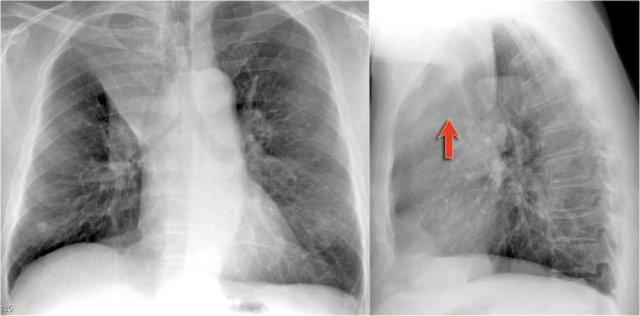

Xẹp thùy giữa phổi phải

Hãy quan sát kỹ các hình X-quang trước, sau đó tiếp tục đọc.

Các dấu hiệu là gì?

- Xóa mờ bờ tim phải (dấu hiệu bóng mờ)

- Đám mờ hình tam giác trên phim nghiêng do xẹp thùy giữa

Thông thường, xẹp thùy giữa phổi phải không gây nâng cao cơ hoành phải đáng kể.

Ngực lõm (pectus excavatum) có thể bắt chước hình ảnh xẹp thùy giữa trên phim thẳng, nhưng phim nghiêng sẽ giúp phân biệt được vấn đề này.